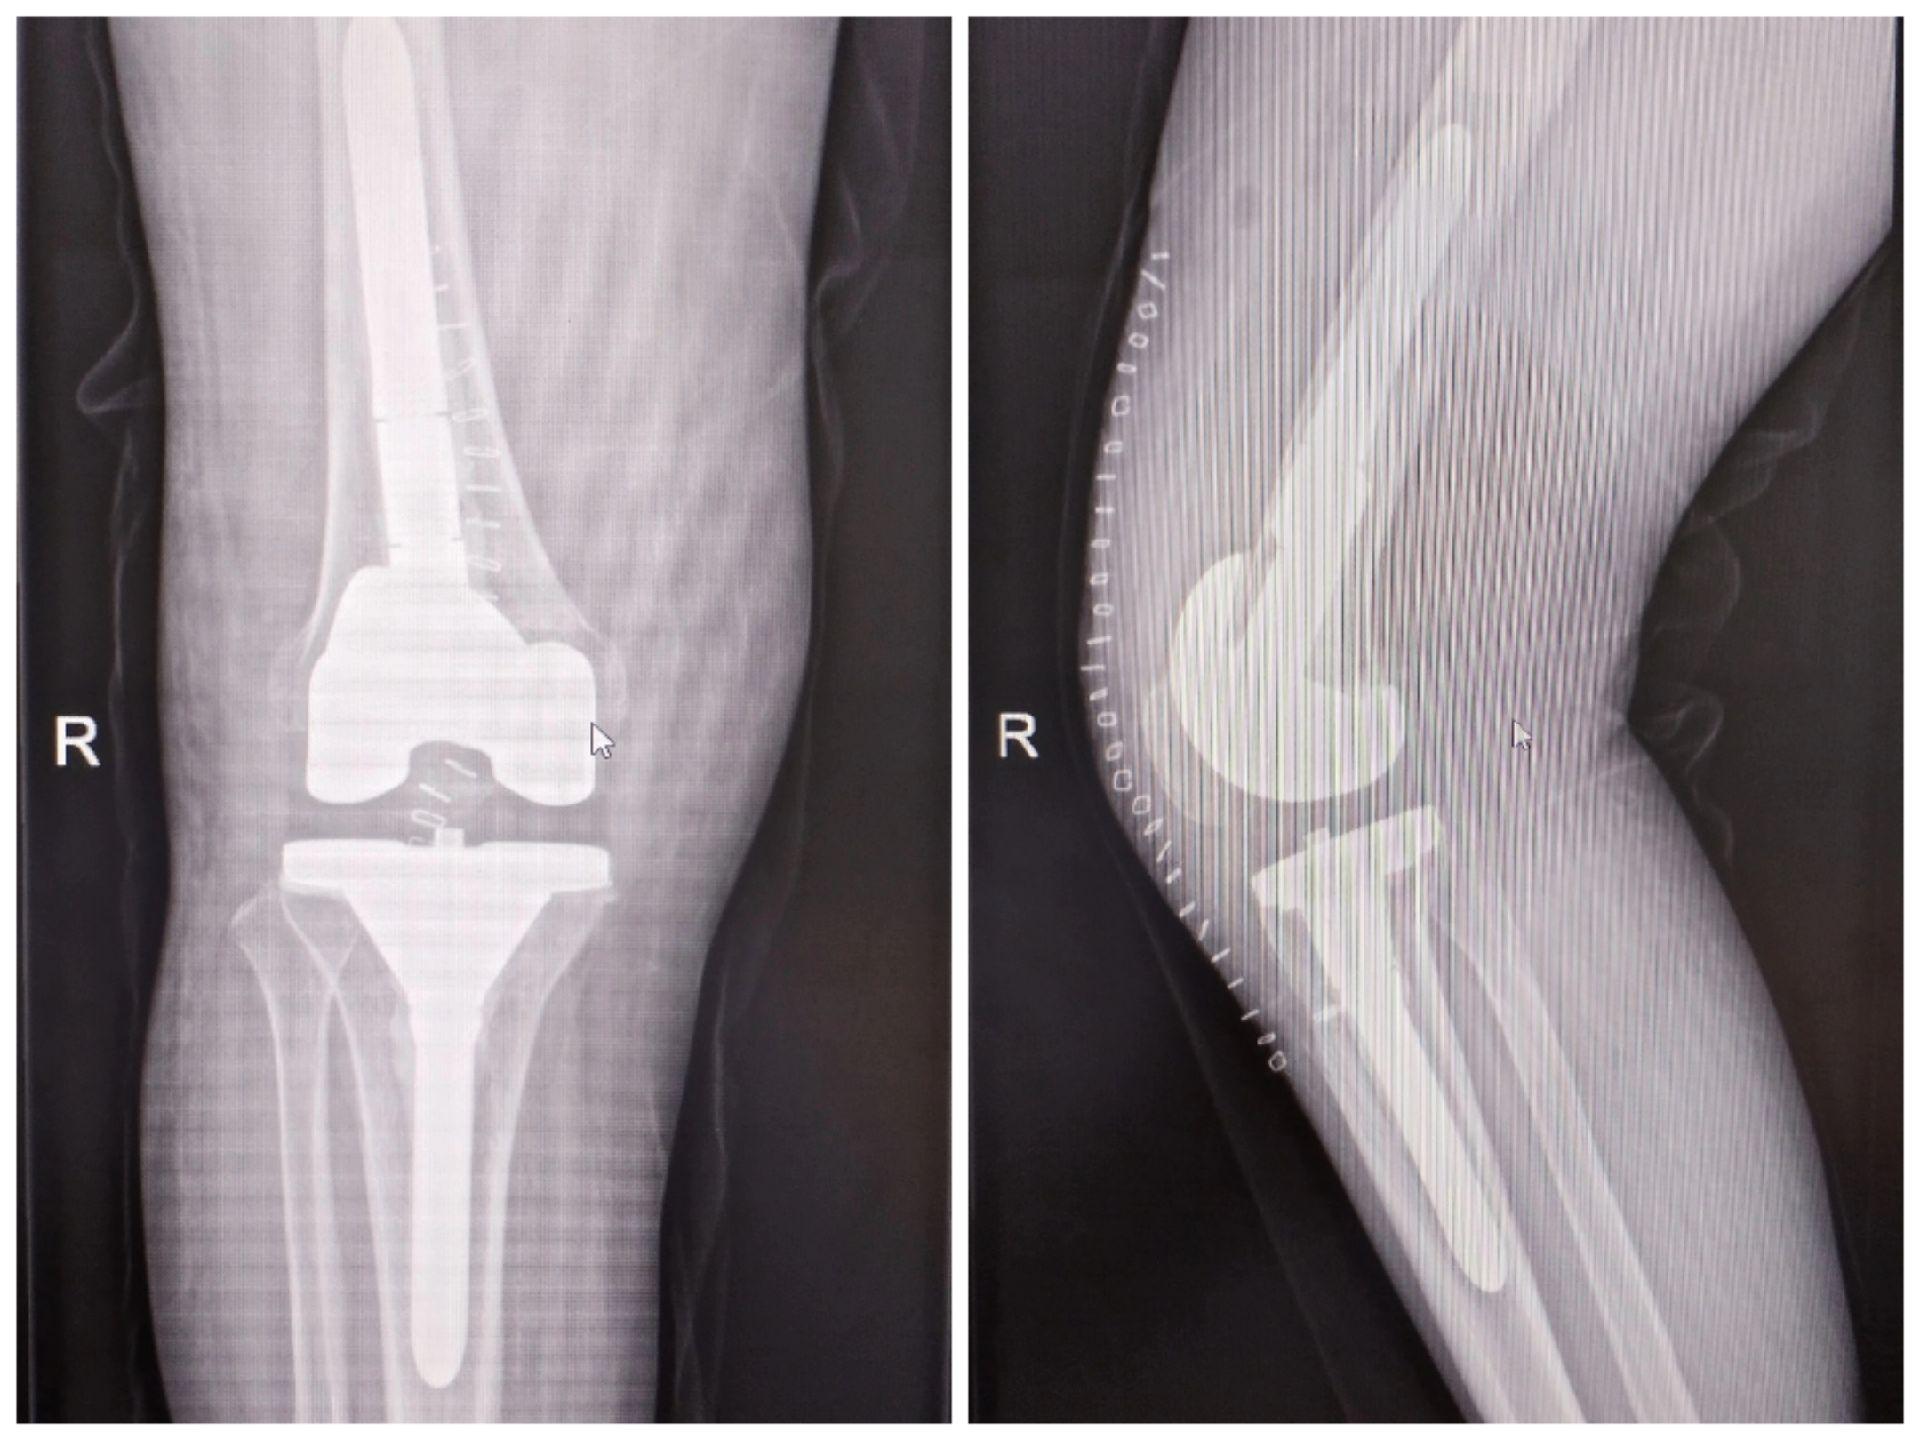

膝关节翻修术。双膝关节置换术后布氏杆菌感染(外院),清创旷置后二期翻修,重新走出自信的步伐。膝关节翻修

膝关节翻修术。双膝关节置换术后布氏杆菌感染(外院),清创旷置后二期翻修,重新走出自信的步伐。